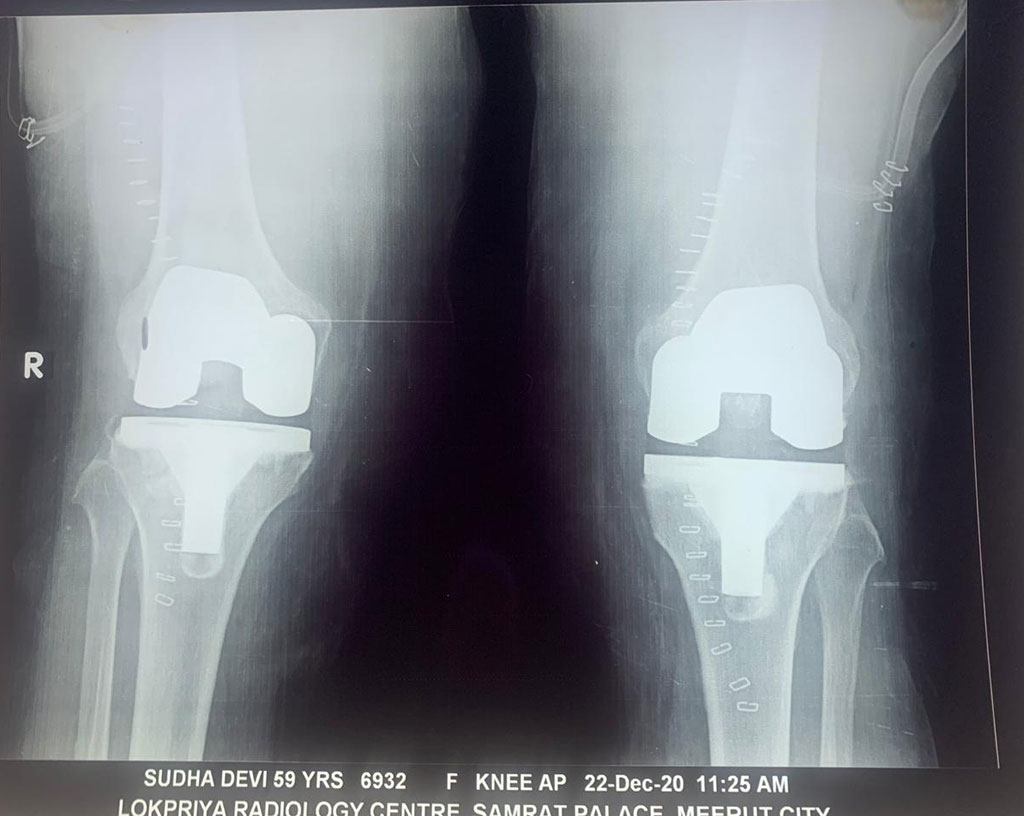

Total Knee Replacement

Name: Sudha Devi

Date of Operation: Dec 2020

Age: 59 Years

After Surgery